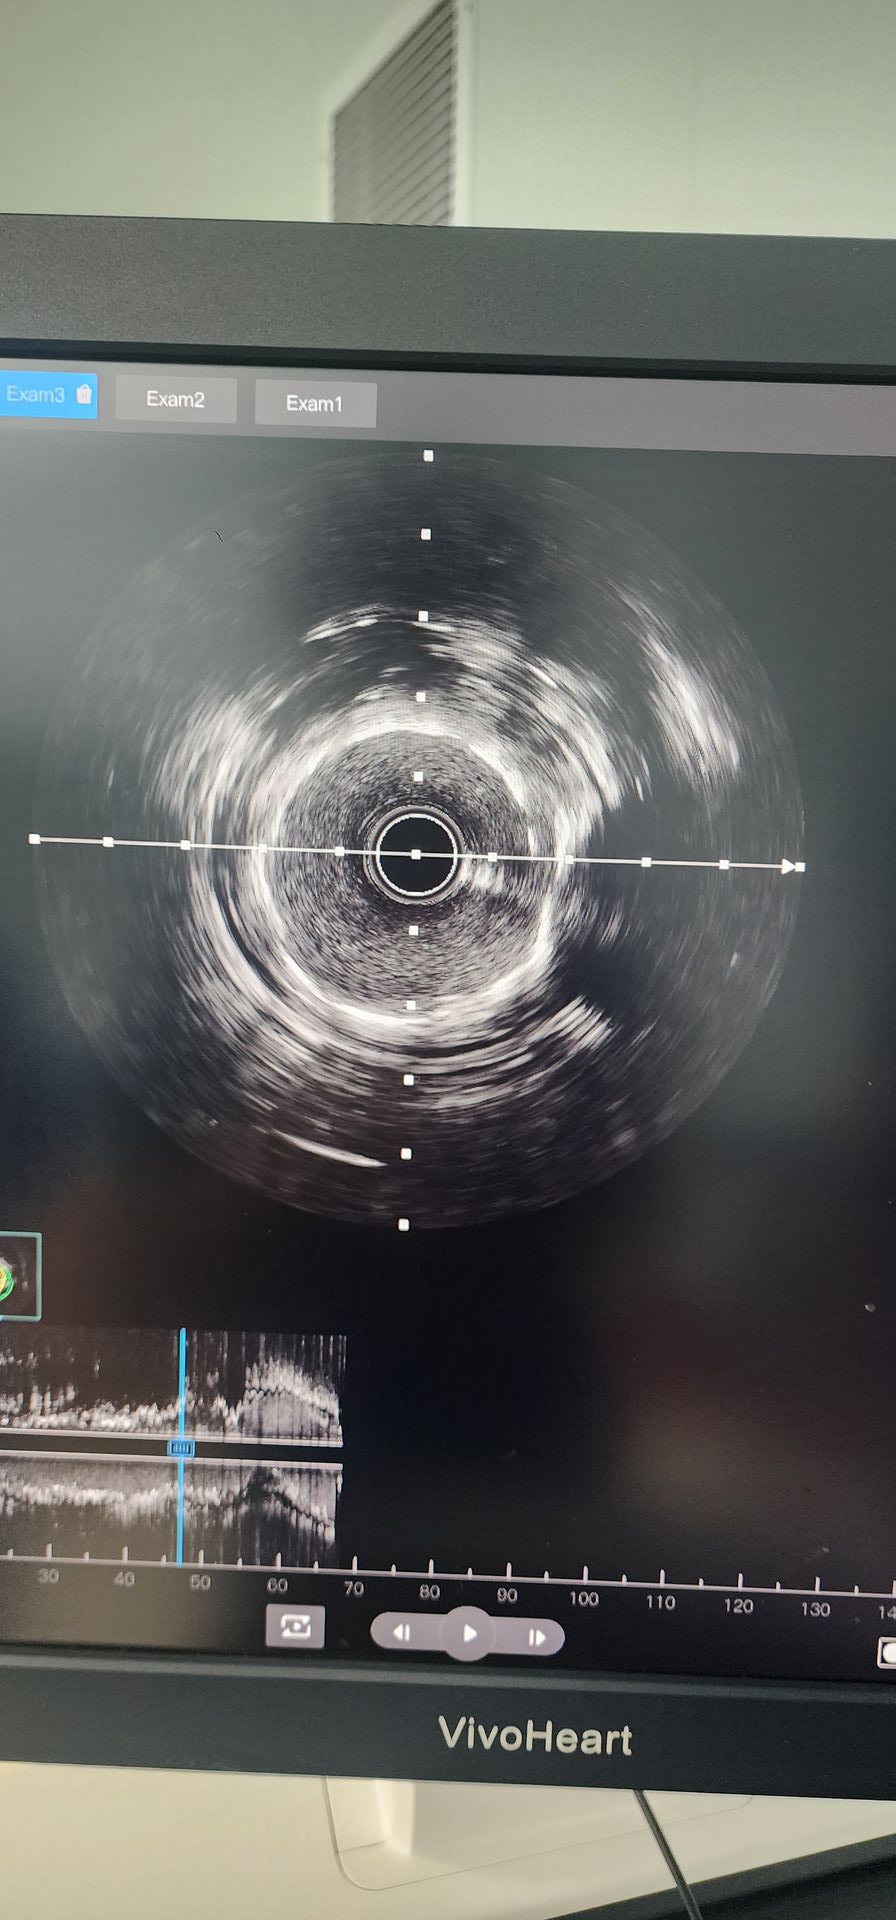

L'angiographie coronaire a révélé une calcification sévère avec une sténose de 95% dans l'artère circonflexe proximale et une sténose calcifiée de 85% à 90% dans l'artère coronaire médiane droite.

Artère circumflex proximale: La prédilatation initiale avec un ballon de 2,0 × 20 a donné de mauvais résultats. Un cathéter de dilatation coronaire IVL à ballonnet de 2,5 × 12 Lepu Vesscrack a ensuite été utilisé, délivrant quatre cycles, fracturant avec succès la lésion calcifiée. Après une amélioration significative de la sténose, un stent de 2,5x14 a été implanté avec succès, avec des résultats angiographiques satisfaisants.

Artère coronaire mi-droite: La pré-dilatation initiale avec un ballon de 2,5 × 20 a entraîné une amélioration limitée. Un cathéter de dilatation coronaire IVL à ballonnet de 2,5 × 12 Lepu Vesscrack a ensuite été utilisé pendant deux cycles, améliorant de manière significative la sténose dans la lésion calcifiée. Un stent de 3,0x19 a ensuite été implanté avec succès, donnant des résultats angiographiques satisfaisants.